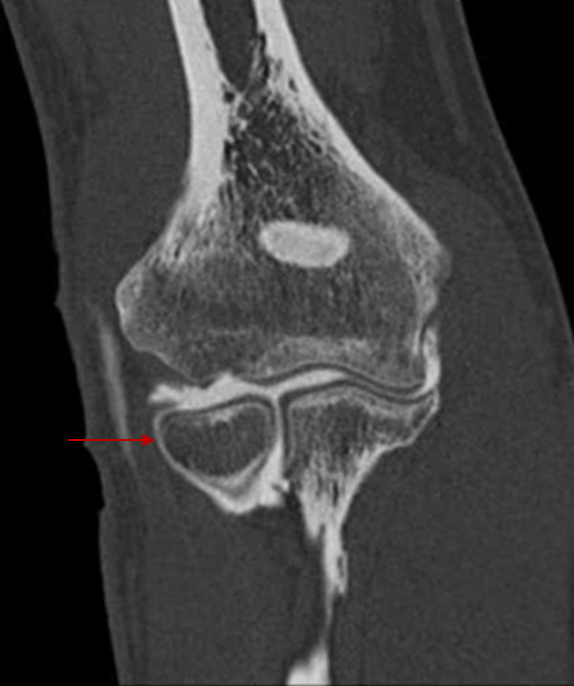

2.125 Die in der folgenden Abbildung mit einem Pfeil markierte Stelle...

- (A) Besitzt eine Gelenkfläche, die vollständig mit hyalinem Knorpel überzogen ist

- (B) Bildet zusammen mit der Ulna ein funktionelles Eigelenk

- (C) Liegt innerhalb der Kapsel des Articulatio humeroradialis

- (D) Ist der Ursprung für die oberflächliche Gruppe der Extensoren des Unterarms

- (E) Wird typischerweise durch das Lig. Anulare radii umfasst